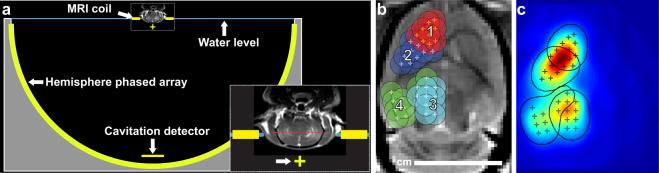

We investigated controlled blood-brain barrier (BBB) disruption using a low-frequency clinical transcranial MRI-guided focused ultrasound (TcMRgFUS) device and evaluated enhanced delivery of irinotecan chemotherapy to the brain and a rat glioma model. Animals received three weekly sessions of FUS, FUS and 10 mg/kg irinotecan, or irinotecan alone. In each session, four volumetric sonications targeted 36 locations in one hemisphere. With feedback control based on recordings of acoustic emissions, 98% of the sonication targets (1045/1071) reached a pre-defined level of acoustic emission, while the probability of wideband emission (a signature for inertial cavitation) was than 1%. BBB disruption, evaluated by mapping the R1 relaxation rate after administration of an MRI contrast agent, was significantly higher in the sonicated hemisphere (P < 0.01). Histological evaluation found minimal tissue effects. Irinotecan concentrations in the brain were significantly higher (P < 0.001) with BBB disruption, but SN-38 was only detected in <50% of the samples and only with an excessive irinotecan dose. Irinotecan with BBB disruption did not impede tumor growth or increase survival. Overall these results demonstrate safe and controlled BBB disruption with a low-frequency clinical TcMRgFUS device. While irinotecan delivery to the brain was not neurotoxic, it did not improve outcomes in the F98 glioma model.

我们使用低频临床经颅 MRI 引导聚焦超声(TcMRgFUS)设备研究了可控的血脑屏障(BBB)破坏,并评估了伊立替康化疗药物递送至大脑的效果和在大鼠脑胶质瘤模型中的效果。动物接受了每周三次的 FUS、FUS 和 10mg/kg 伊立替康或单独伊立替康治疗。在每次治疗中,四个容积式超声波靶向一个半球中的 36 个位置。通过基于声发射记录的反馈控制,98%的声发射目标(1045/1071)达到了预先定义的声发射水平,而宽带发射的概率(惯性空化的特征)大于 1%。通过给药 MRI 对比剂后测量 R1 弛豫率来评估 BBB 破坏,发现超声波治疗半球的 BBB 破坏明显更高(P<0.01)。组织学评估发现组织影响最小。BBB 破坏后,大脑中的伊立替康浓度显著升高(P<0.001),但仅在<50%的样本中检测到 SN-38,且仅在过量的伊立替康剂量下才检测到。伊立替康与 BBB 破坏并不会阻碍肿瘤生长或增加存活率。总的来说,这些结果表明低频临床 TcMRgFUS 设备可安全且可控地破坏 BBB。尽管伊立替康递送至大脑并未引起神经毒性,但它并未改善 F98 脑胶质瘤模型的结果。